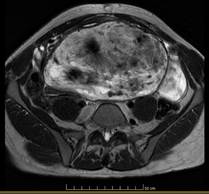

Posteriormente se realizó una resonancia magnética de abdomen y pelvis, en la que se observó una masa pélvica extraperitoneal con extensión abdominal, de 230mm x 183mm x 106mm de tamaño, muy bien delimitada, provocando desplazamiento severo de recto, de útero y anexos, y de vejiga. Dicha tumoración se mostró hipointensa en T1 e hiperintensa en T2 (imágenes 1 2 y 3).

En cuanto a la imagenología, la resonancia magnética permite una mejor planificación quirúrgica gracias a su alta precisión para identificar invasión de estructuras adyacentes1. Es frecuente encontrar una masa iso o hipointensa en T1 e hiperintensa en T2 gracias a su gran contenido en matriz y de agua, y es posible encontrar un patrón característico en espiral o remolino, manifestando su componente fibrovascular13. Otros estudios de utilidad debatida son la ecografía abdominal, en la que se halla una imagen hipoecoica o quística y vascularización periférica al Doppler7, y la tomografía computada, identificando una masa hipodensa y heterogénea de márgenes bien definidos y su característica forma arremolinada ante la administración de contraste7.